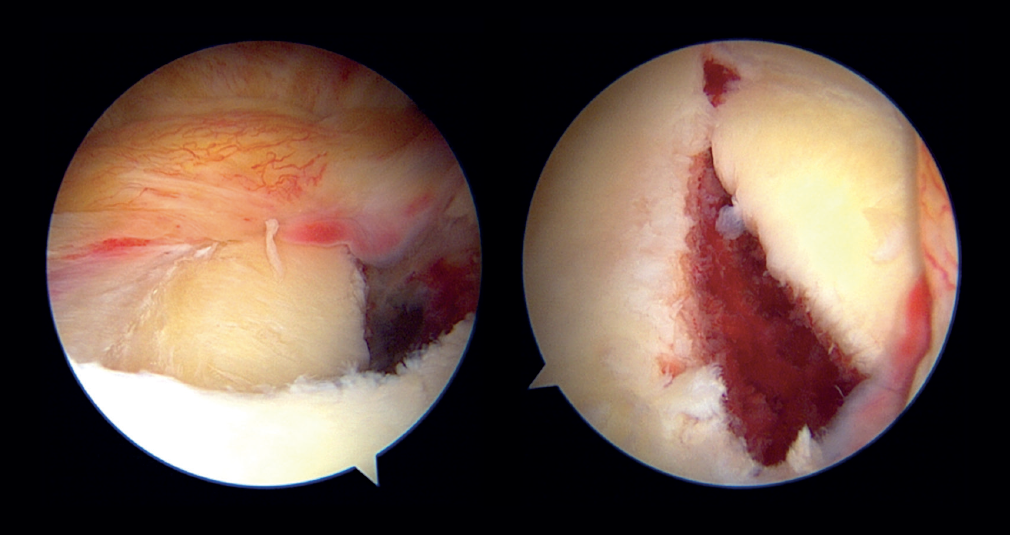

Direct trauma to the shoulder, with impacting of the humeral head in the glenoid cavity in some cases results in glenoid fracture and consequent glenohumeral dislocation. Glenoid bony lesions of this kind often evolve towards relapsing glenohumeral instability(1). When the size of the glenoid fracture proves relevant, with a classically established critical value of 20-25% of the area(2) and a currently defined value of 15% or more(3), surgery is the ideal treatment for avoiding the subsequent relapse of instability(4,5). Porcellini et al. in 2002(4) and Sugaya et al. in 2005(5) described the arthroscopic repair technique for lesions of this kind, consisting of reduction and block osteocapsular-ligamentous-labral fixation (Figure 1). Posteriorly, more sophisticated modifications of the technique were developed, such as the double-row / double pulley procedure of Ganokroj(6), consisting of a block reconstruction based on fixation at two different points: an anchoring medial with respect to the chondral margin of the glenoid cavity, and a lateral anchoring in the glenoid margin. Furthermore, other open and arthroscopic technical modifications have been described for such lesions(7).

In the classical Porcellini-Sugaya technique, debridement and roughening of the bone margins of the fracture was carried out with synoviotome, rasps and curettes (Figure 2). All-suture anchorings were used for the repair. The first anchoring was placed in the lowermost zone of the defect (Figure 3), and one its extremities extended to the damaged labrum in the lowermost zone, followed by knotting. The second anchoring was placed in the uppermost zone of the defect (Figure 4), in the same way as the first, followed by knotting. In those cases where considered necessary, one or two more anchorings were added proximal to the previous ones. Reduction and stability of the fragment was checked.